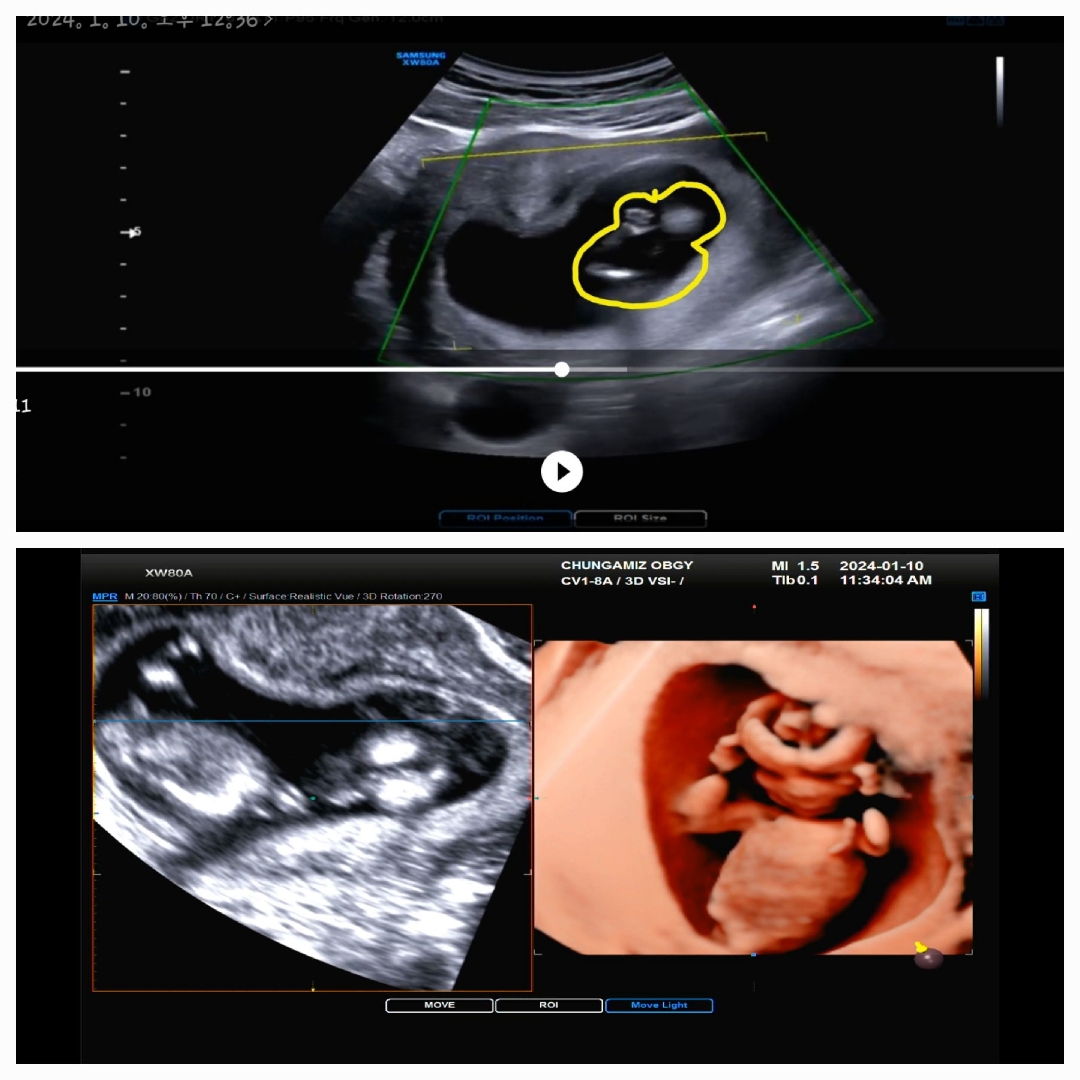

12주 1차기형아검사 목투명대 검사 입체초음파

수요일 12주 3일에 1차기형아검사하고 왔네요 목투명대는 1.04/1.57/1.25 로 무사히 통과했어요 다들 12주차 때 각도법 물어보시던데ㅋ 저는 도무지 봐도 모르겠더라구요ㅋㅋ 입체 초음파에서도 어찌나 다르꼬고 귀틀막하고 있던지ㅋㅋ 언니가 촘파보면서 손가락 빠는사진도 캡쳐해서 보내줬는데 너무 귀여위요ㅋ 저는16일주에나 성별을 알수있겠죠?ㅋㅋ 10주3일차엔 5일정도 커서 걱정했는데 요번엔 딱 주수에 맞게 커있어서 너무 기분 좋았네요 1차 2차 기형아 검사 무사통과 했으면 좋겠네요🙏 다른 맘님들도 모두 화이팅 하세요^---^